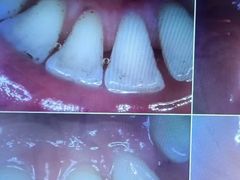

• 好大夫口腔(广州店)

• -好大夫口腔(广州店)

jiaoshen君君 | 23-11-17

报错